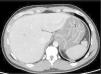

Se trata de un paciente de 36 años sin historia médica de inmunosupresión que acude al servicio de urgencias con dolor epigástrico intenso y fiebre. Debido a la elevación persistente de los reactantes de fase aguda, se realizó una tomografía computarizada (TC) abdominal, observando edema de submucosa y engrosamiento de la pared gástrica, sugerentes de un proceso de inflamación gástrica (fig. 1). El paciente presentó un rápido deterioro y fue transferido a la unidad de cuidados intensivos (UCI). Posteriormente, se realizó una endoscopía superior, encontrando pliegues gástricos engrosados (fig. 2). El estudio histológico de las biopsias gástricas mostró inflamación aguda y necrosis en mucosa y submucosa (fig. 3), con cultivos positivos para Streptococcus pyogenes. A pesar del tratamiento con antibióticos, la respuesta fue mala y en consecuencia se sometió a cirugía de urgencia con gastrectomía total. La recuperación del paciente fue adecuada y fue dado de alta, sin incidentes.